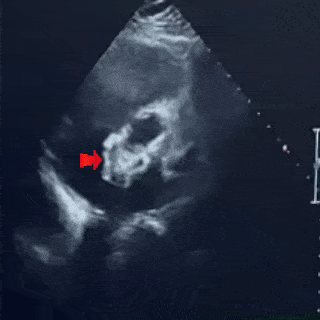

四腔心切面

合并房间隔膨出瘤

缺损+房间隔膨出瘤24.7mm

四腔心切面下

封堵器左右盘面骑跨房间隔两侧形态位置良好